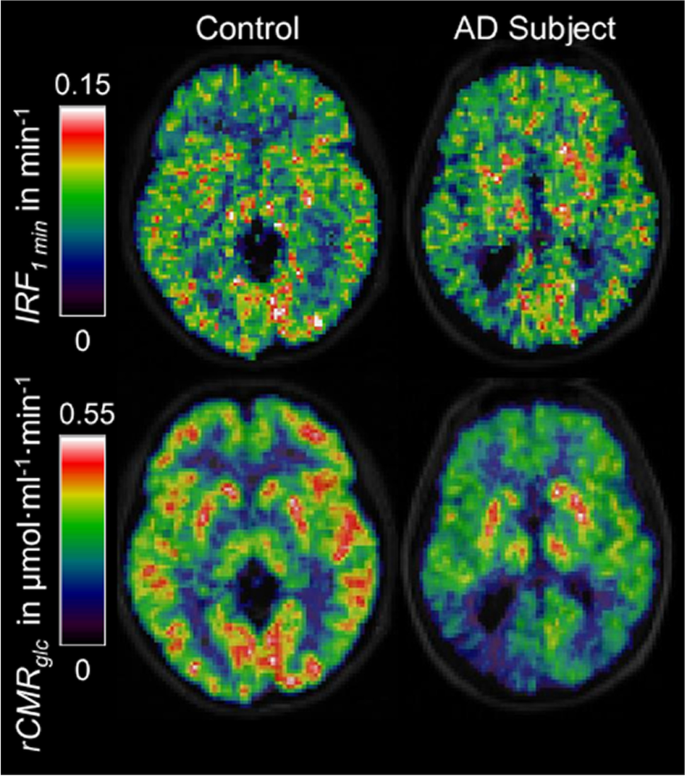

[18F]-fluorodeoxyglucose (FDG) is the [18F] radiolabelled form of 2-DG, a functional substrate of GLUT1, hence it is extracted from the blood across the BBB via the same mechanisms as glucose, but does not undergo further metabolisation after phosphorylation into FDG-6P by hexokinase [271,272,273]. In contrast to glucose, this results in the accumulation of [18F]FDG in cells allowing accurate quantitative measurements of cerebral metabolic rate for glucose utilization (CMRGlu). [18F]FDG PET has demonstrated cerebral glucose hypometabolism in AD in a reproducible symptom-relevant pattern (Fig. 9) [274,275,276] with the capacity to distinguish AD from MCI and cognitively normal individuals [277, 278]. [18F]FDG PET has, therefore, excellent diagnostic potential and has been used extensively to stratify MCI and AD patients before β-amyloid specific tracers such as [11C]PIB or [18F]Florbetaben became available [76, 279,280,281]. Hypometabolism has been observed in several neurodegenerative diseases and its anatomical distribution is disease-specific. Moreover, hypometabolism indicated by FDG-PET is a good predictor of imminent cognitive decline [72, 278], unlike amyloid, which may build up in the AD brain for decades prior to clinical symptoms. However, it remains unclear whether hypometabolism is a cause or consequence of reduced neuronal activity linked to synaptic loss [282, 283]. This is further complicated by the proposed multicellular mechanism of glucose and lactate transport, known as the astrocyte-neurone lactate shuttle (ANLS) [66, 78, 232]. Furthermore, the measures are affected by CBF and the permeability surface-area product of glucose, which are both affected by ageing and disease [29, 284].

[mM] is the glucose concentration in whole blood, [mM] is the glucose concentration in the parenchyma, [μmol/min/mL] is the maximal rate of transport,[mM] is the half saturation constant of glucose transport, and CMRglc [μmol/min/mL] is the cerebral metabolic rate of glucose utilisation. Kinetic analysis of this type may enable estimation of transport and metabolic rates, providing information on the density of glucose transporters and the relative number of each type (Fig. 6). However, it is currently challenging to obtain reliable image-derived input functions (i.e. estimates of Cb(t)), which is particularly important due to individual differences in insulin responses [242]. Therefore, new approaches that provide more robust detection of image-based input functions are needed if kinetic analyses of glucoCEST and/or glucoCESL data are to be useful as research and clinical markers of glucose uptake and metabolism.